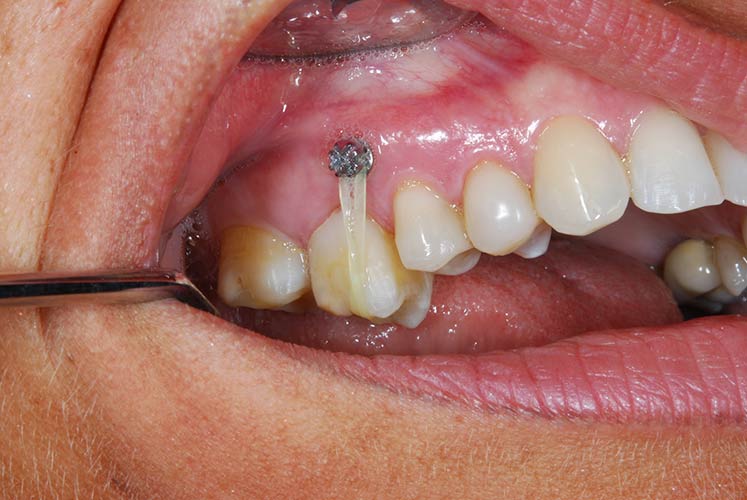

Con protesi fissa superiore e protesi fissa inferiore

I denti irrecuperabili dell'arcata superiore ed inferiore del paziente di anni 65

sono stati sostituiti da 10 impianti, cioè protesi radicolari endo-ossee che sostengono le protesi fisse superiore ed inferiore.